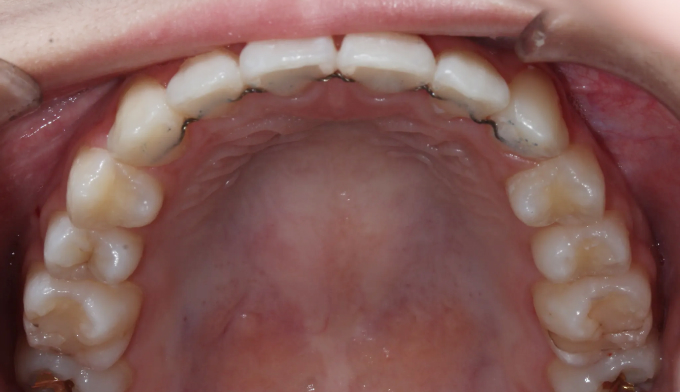

이번 케이스에서는 덧니가 심하고 공간이 매우 부족하지만, 입의 크기가 작고 입술이 얇은 편이었기 때문에 발치 없이 교정하기로 계획하였습니다.

입천장 확장과 치아배열을 통하여 총 18개월동안 치료하였습니다.